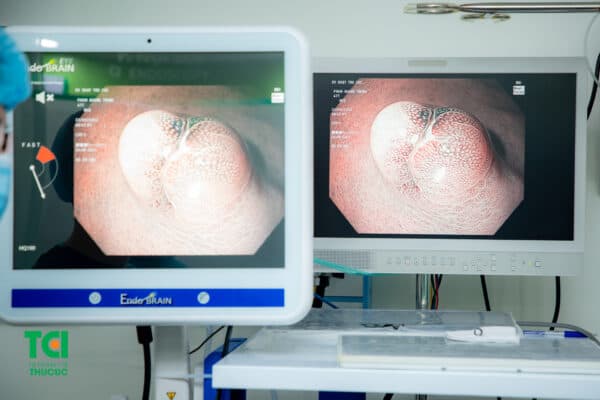

Hình ảnh polyp ở dạ dày được phát hiện qua nội soi đường tiêu hóa trên.